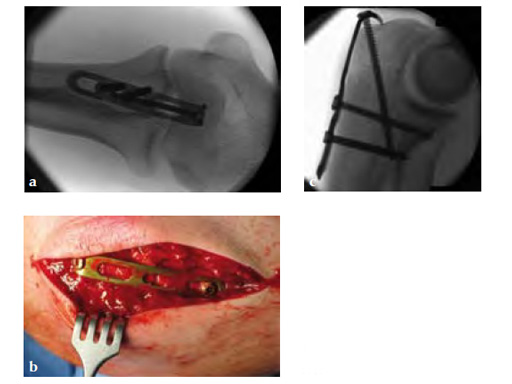

Fig 3ab X-rays 5 months postoperatively.

Fig 4ab Implant removal 5.5 months postoperatively.